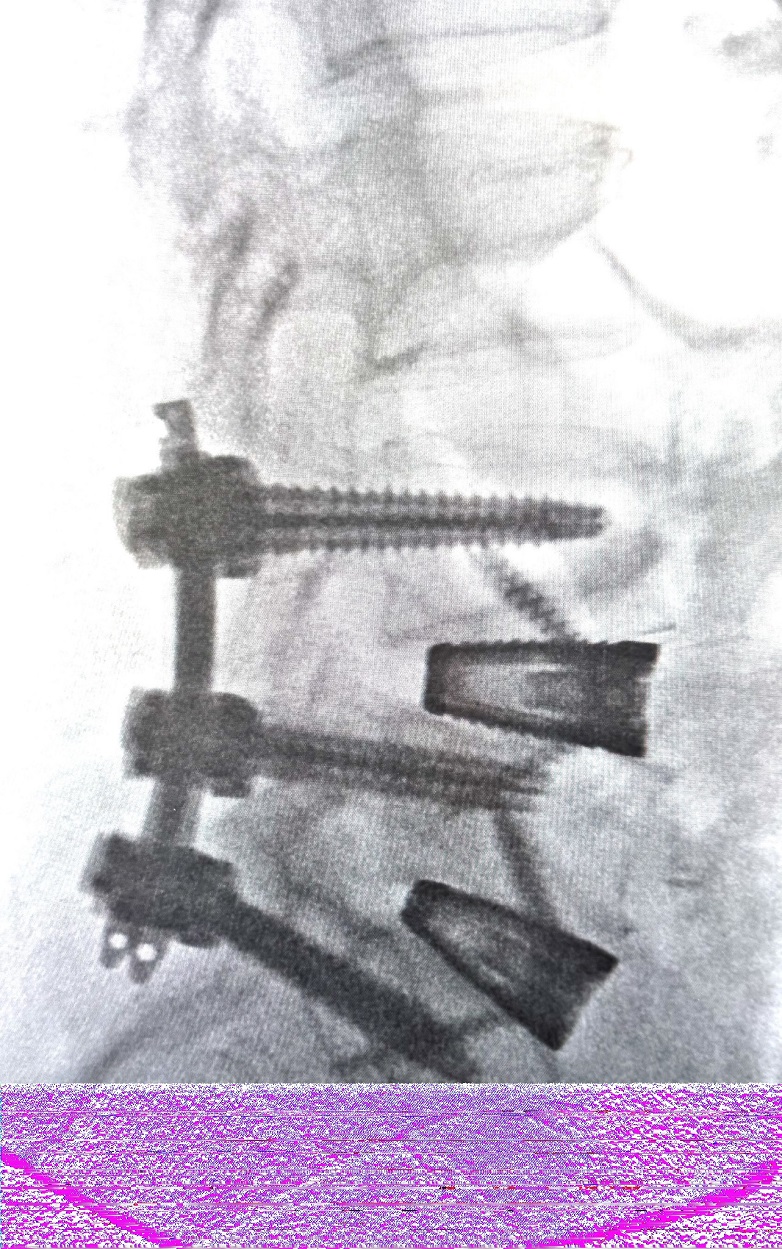

腰椎稳定手术中X射线成像可见脊柱融合硬件。图片由Spinal Elements提供